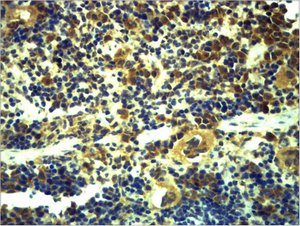

Main InformationTargetTLR6Host SpeciesRabbitReactivityHuman, Mouse, RatApplicationsIHC, IFConjugate/ModificationUnmodifiedDetailed InformationRecommended Dilution RatioIHC 1:200-500; IF 1:50-200FormulationPBS, pH 7.4, containing 0.5%BSA, 0.02% sodium azide as Preservative and 50% Glycerol.SpecificityThe antibody detects endogenous TLR6 protein.PurificationThe antibody was affinity-purified from rabbit antiserum by affinity-chromatography using epitope-specific immunogen.Storage-15°C to -25°C/1 year(Do not lower than -25°C)ModificationUnmodifiedClonalityPolyclonalIsotypeIgGAntigen&Target InformationImmunogen:Recombinant Protein of TLR6Specificity:The antibody detects endogenous TLR6 protein.Gene Name:TLR6Protein Name:Toll-like receptor 6Other Name:Toll-like receptor 6 ; CD286Background:The protein encoded by this gene is a member of the Toll-like receptor (TLR) family which plays a fundamental role in pathogen recognition and activation of innate immunity. TLRs are highly conserved from Drosophila to humans and share structural and functional similarities. They recognize pathogen-associated molecular patterns (PAMPs) that are expressed on infectious agents, and mediate the production of cytokines necessary for the development of effective immunity. The various TLRs exhibit different patterns of expression. This receptor functionally interacts with toll-like receptor 2 to mediate cellular response to bacterial lipoproteins. A Ser249Pro polymorphism in the extracellular domain of the encoded protein may be associated with an increased of asthma is some populations.[provided by RefSeq, Jan 2011],Function:Function:Participates in the innate immune response to Gram-positive bacteria and fungi. Acts via MYD88 and TRAF6, leading to NF-kappa-B activation, cytokine secretion and the inflammatory response. Recognizes mycoplasmal macrophage-activating lipopeptide-2kD (MALP-2), soluble tuberculosis factor (STF), phenol-soluble modulin (PSM) and B.burgdorferi outer surface protein A lipoprotein (OspA-L) cooperatively with TLR2.,similarity:Belongs to the Toll-like receptor family.,similarity:Contains 1 TIR domain.,similarity:Contains 13 LRR (leucine-rich) repeats.,subunit:Binds TLR2 via their respective extracellular domains. Binds MYD88 via their respective TIR domains.,tissue specificity:Detected in monocytes, CD11c+ immature dendritic cells, plasmacytoid pre-dendritic cells and dermal microvessel endothelial cells.,Cellular Localization:Cell membrane ; Single-pass type I membrane protein . Cytoplasmic vesicle, phagosome membrane ; Single-pass type I membrane protein . Membrane raft . Golgi apparatus . Upon complex formation with CD36 and TLR4, internalized through dynamin-dependent endocytosis. Does not reside in lipid rafts before stimulation but accumulates increasingly in the raft upon the presence of the microbial ligand. In response to diacylated lipoproteins, TLR2:TLR6 heterodimers are recruited in lipid rafts, this recruitment determine the intracellular targeting to the Golgi apparatus (PubMed:16880211). .Tissue Expression:Detected in monocytes, CD11c+ immature dendritic cells, plasmacytoid pre-dendritic cells and dermal microvessel endothelial cells.Research Areas:>>Phagosome ; >>Toll-like receptor signaling pathway ; >>Salmonella infection ; >>Chagas disease ; >>Tuberculosis ; >>Lipid and atherosclerosis